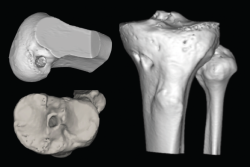

El estudio mediante TC, tanto en 2D como en las reconstrucciones actuales en 3D, va a ser de gran utilidad para poder identificar la posición de los túneles óseos tibial y femoral, la dirección de ambos y, finalmente, el grado de dilatación y la morfología de los mismos. Estos aspectos van a ser claves para poder planificar la cirugía de revisión en uno o dos tiempos (Figuras 3 y 4).

Figura 4. Actualmente, la reconstrucción en 3D de la tomografía computarizada permite comprender mejor la localización tridimensional de los túneles óseos.